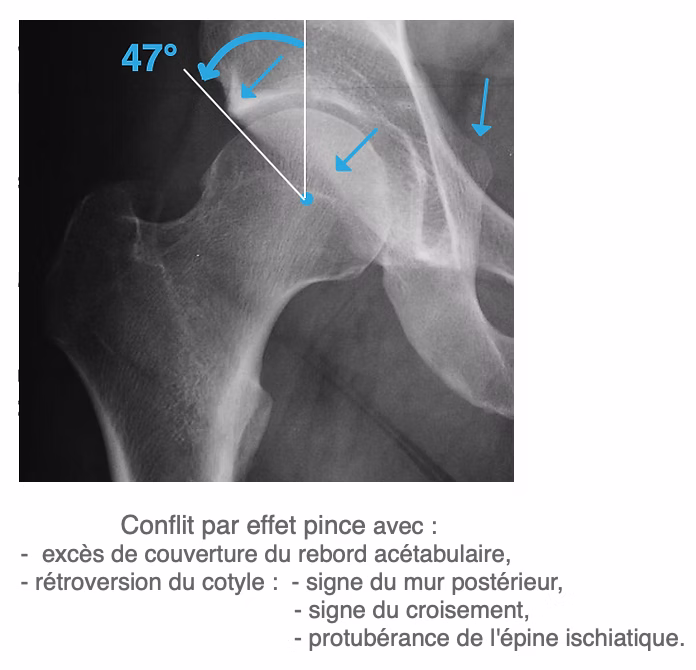

- 2. Le conflit de type PINCER (b) : bord de l'acétabulum trop proéminent ou cotyle trop profond